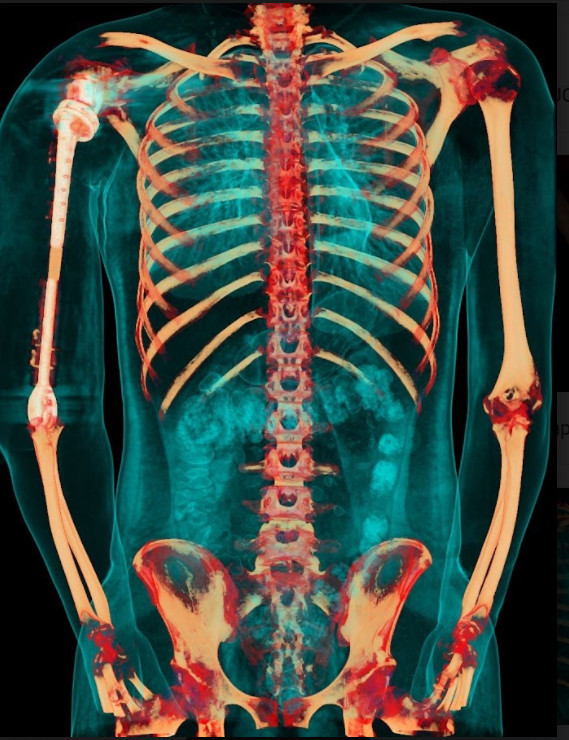

Ảnh chụp X-quang so sánh xương cánh tay 2 bên sau khi phẫu thuật

Ca phẫu thuật phục hồi cánh tay cho bệnh nhân V.T.Đ là ca bệnh đầu tiên trên thế giới sử dụng kết hợp vật liệu giữa hợp kim titan và vật liệu y sinh PEEK do các bác sỹ của Trung tâm CTCH&YHTT Vinmec thực hiện

Việc sử dụng kết hợp 2 loại vật liệu trên cùng một xương nhân tạo để tận dụng được ưu điểm tối đa: tính vận động chính xác, linh hoạt của hợp kim titanium tại vùng khớp, và đặc tính nhẹ, bền, tương thích với cơ thể của vật liệu PEEK. Nhờ vậy, trọng lượng cánh tay nhân tạo có thể giảm xuống còn 1 nửa và chi phí giảm tới hơn 1/3 so với việc chỉ dùng vật liệu kim loại như trước đây.